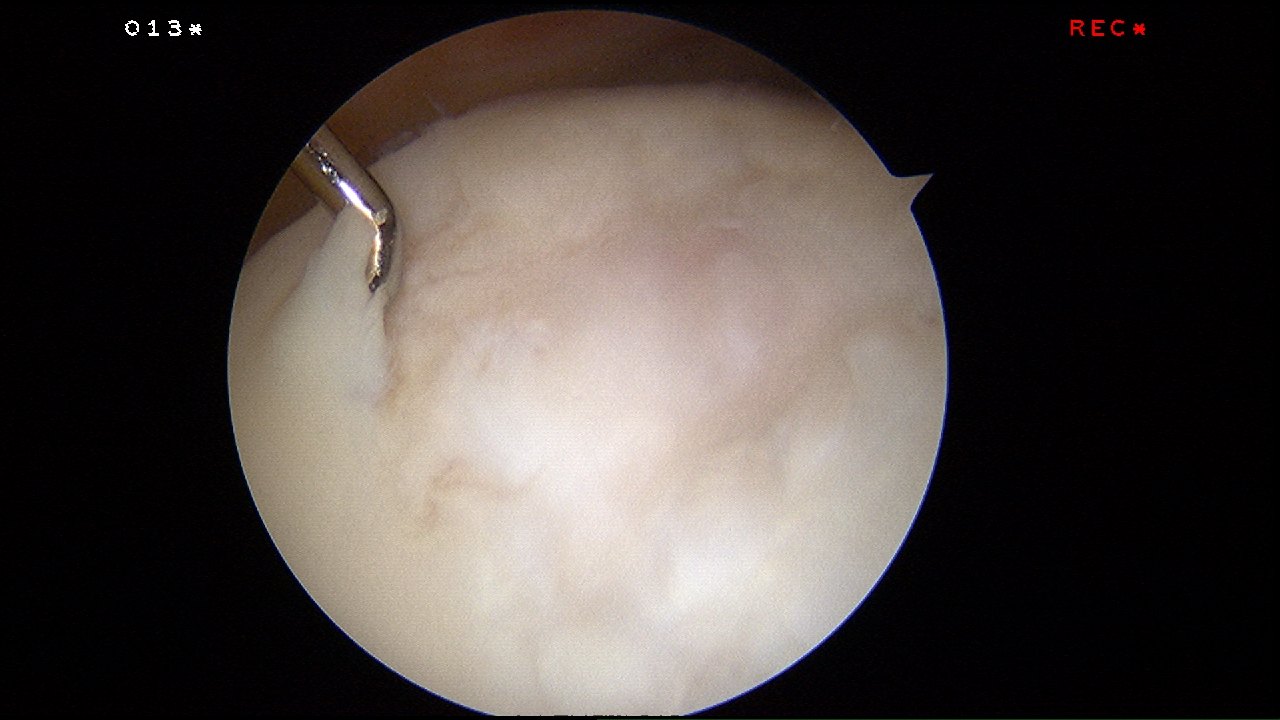

Microfracture surgery is an articular cartilage repair surgical technique that works by creating tiny fractures in the underlying bone.

The beauty of this surgery is that it is done through key-holes (using arthroscopy) and with easily available tools called chondral picks.

MRI scan showed full thickness cartilage wear in the trochlear groove (thigh bone).

Arthroscopic enhanced microfracture was performed.